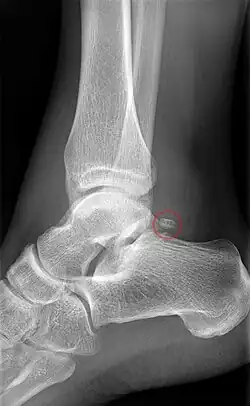

Osul trigon

1 - Osul trigon; 1' – Sincondroza osului trigon cu tuberculul lateral al talusului; 2 - Tuberculul medial al procesului posterior al talusului; 3 - Șanțul tendonului mușchiului flexor lung al halucelui; 4 - Fața laterală a talusului; 5 - Fața superioară a trohleei talusului; 7 - Fața articulară calcaneană posterioară a talusului; 8 - Tuberculul lateral al procesului posterior al talusului.

Osul trigon (Os trigonum) (din latina trigonon = triunghi) este un osișor supranumerar (accesoriu) independent al tarsului situat în partea posterioară a talusului, lângă tuberculul lateral al procesului posterior al talusului. Incidența sa a fost estimată în literatura de specialitate a fi între 1,7 și 8% în populație, iar în 1,4% este bilateral. La examenul radiologic, prezența sa trebuie să se distingă clar de fractură Shepherd (fractura tuberculului lateral) care întrerupe baza procesului posterior al talusului. Tendonul mușchiului flexorul lung al halucelui trece medial de osul trigon.[1][8][9][38][52][53][54][55][56][57][58]

După cum sugerează și numele, osul trigon are de obicei o formă triunghiulară, cu 3 fețe (anterioară, inferioară și posterioară), dar poate avea și o formă rotunjită sau ovală. Osul trigon este compus dintr-o parte corticală periferică și un centru spongios. De obicei, osul trigon are trei fețe: una anterioară, alta inferioară și a treia posterioară. Fața anterioară articulară are de obicei o formă de semilună și formează cu tuberculul lateral al talusului o articulație de tip sincondroză sau este legat de acesta printr-un țesut fibros, fibrocartilaginos sau cartilaginos. Fața inferioară, calcaneană, este și ea articulară, și poate să se articulează cu fața superioară a calcaneului, participând la coaliția (sinostoza) talocalcaneană. Fața posterioară este nearticulară. Osul trigon este cel mai adesea unic și măsoară mai puțin de 1 cm pe axul mare. El poate fi, de asemenea, bipartit (divizat în două părți) sau multipartit (divizat în mai multe părți). Osul trigon fuzionat cu tuberculul lateral este numit proces trigonal[14][52][53][59]

Osul trigon provine dintr-un centru de osificare cartilaginas secundar, care se formează în partea posterioară a talusului, între 11 și 13 ani la băieți și între 8 și 10 ani la fete. În mod normal, acest nucleu de osificare fuzionează cu tuberculul lateral al talusului în cursul primului an de la apariția sa, participând la formarea procesul posterior al talusului. Atunci când această fuziune antrenează formarea unui proces talar posterior mare și intact, acesta este numit procesul talar posterior hipertrofic sau "procesul Stieda." În absența fuziunii centrului de osificare cu tuberculul lateral al talusului, din acest centru de osificare se formează un os independent, numit osul trigon.[52][53]